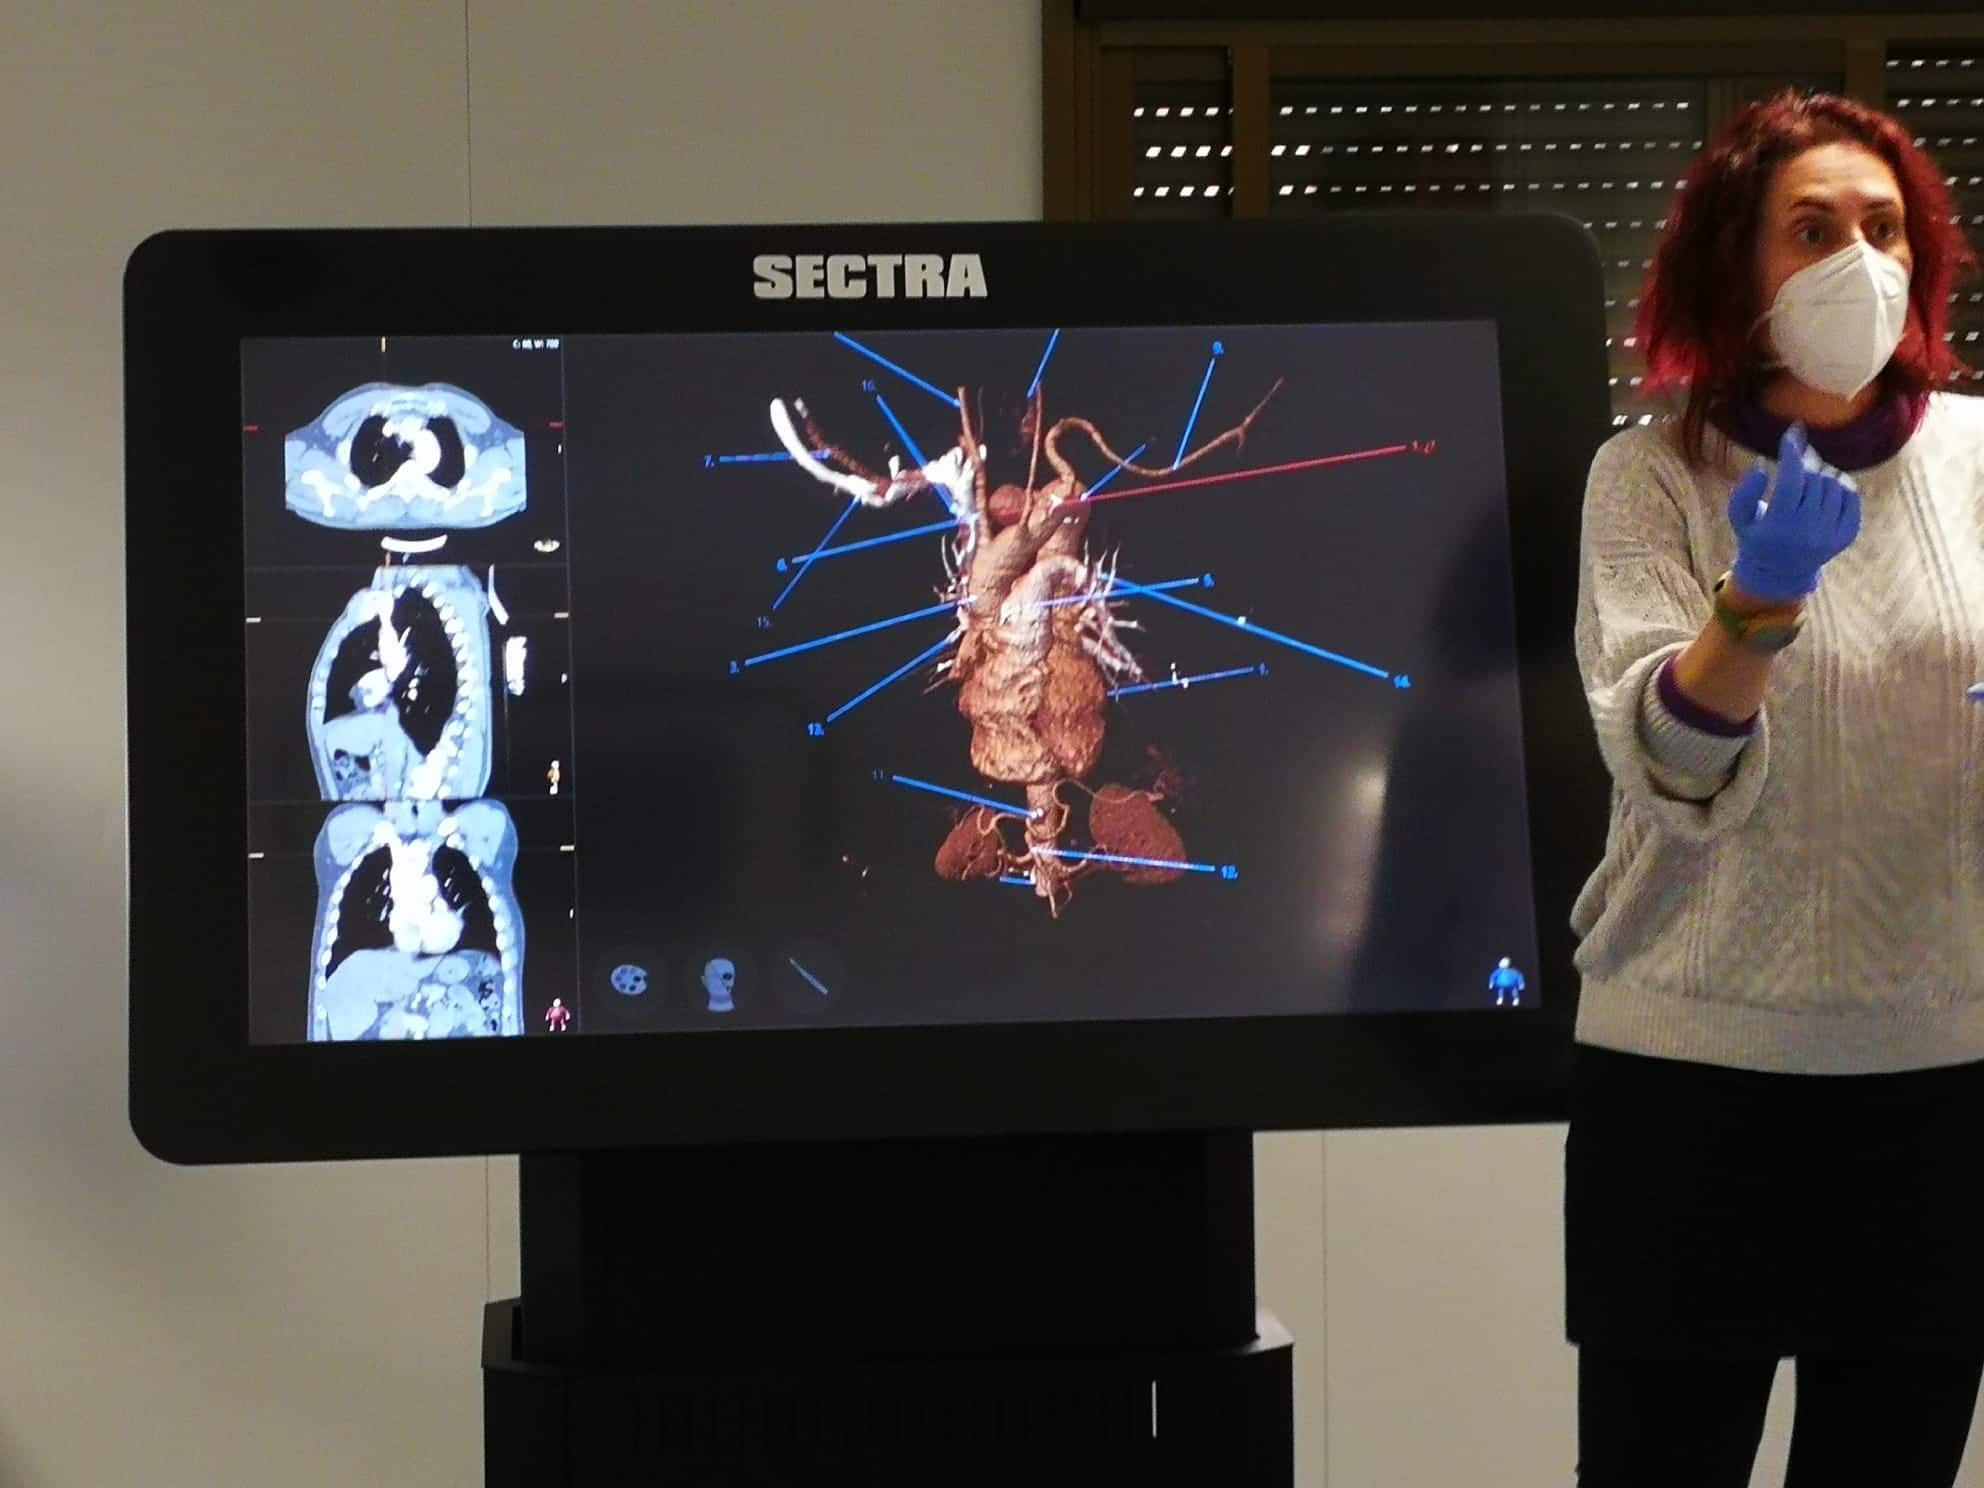

LUGAR: Av. de los Jerónimos, 135, 30107 Guadalupe (Murcia) – Sala de disección de la UCAM (Aulario 6)

DURACIÓN: 20 Horas

DOCENTES: Antonio García Godino, Manuel Moreno Más, Jose María Belmonte Hernández y Andrés Martínez Almagro

DIRIGIDO A: Fisioterapeutas y alumnos de fisioterapia